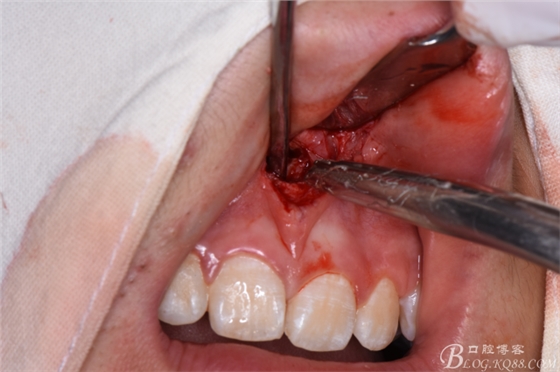

圖14.取出多生牙牙根

圖15.取出11、21之間多生牙后的骨腔

圖16.生理鹽水沖洗創(chuàng)面

圖17.放膠質(zhì)銀